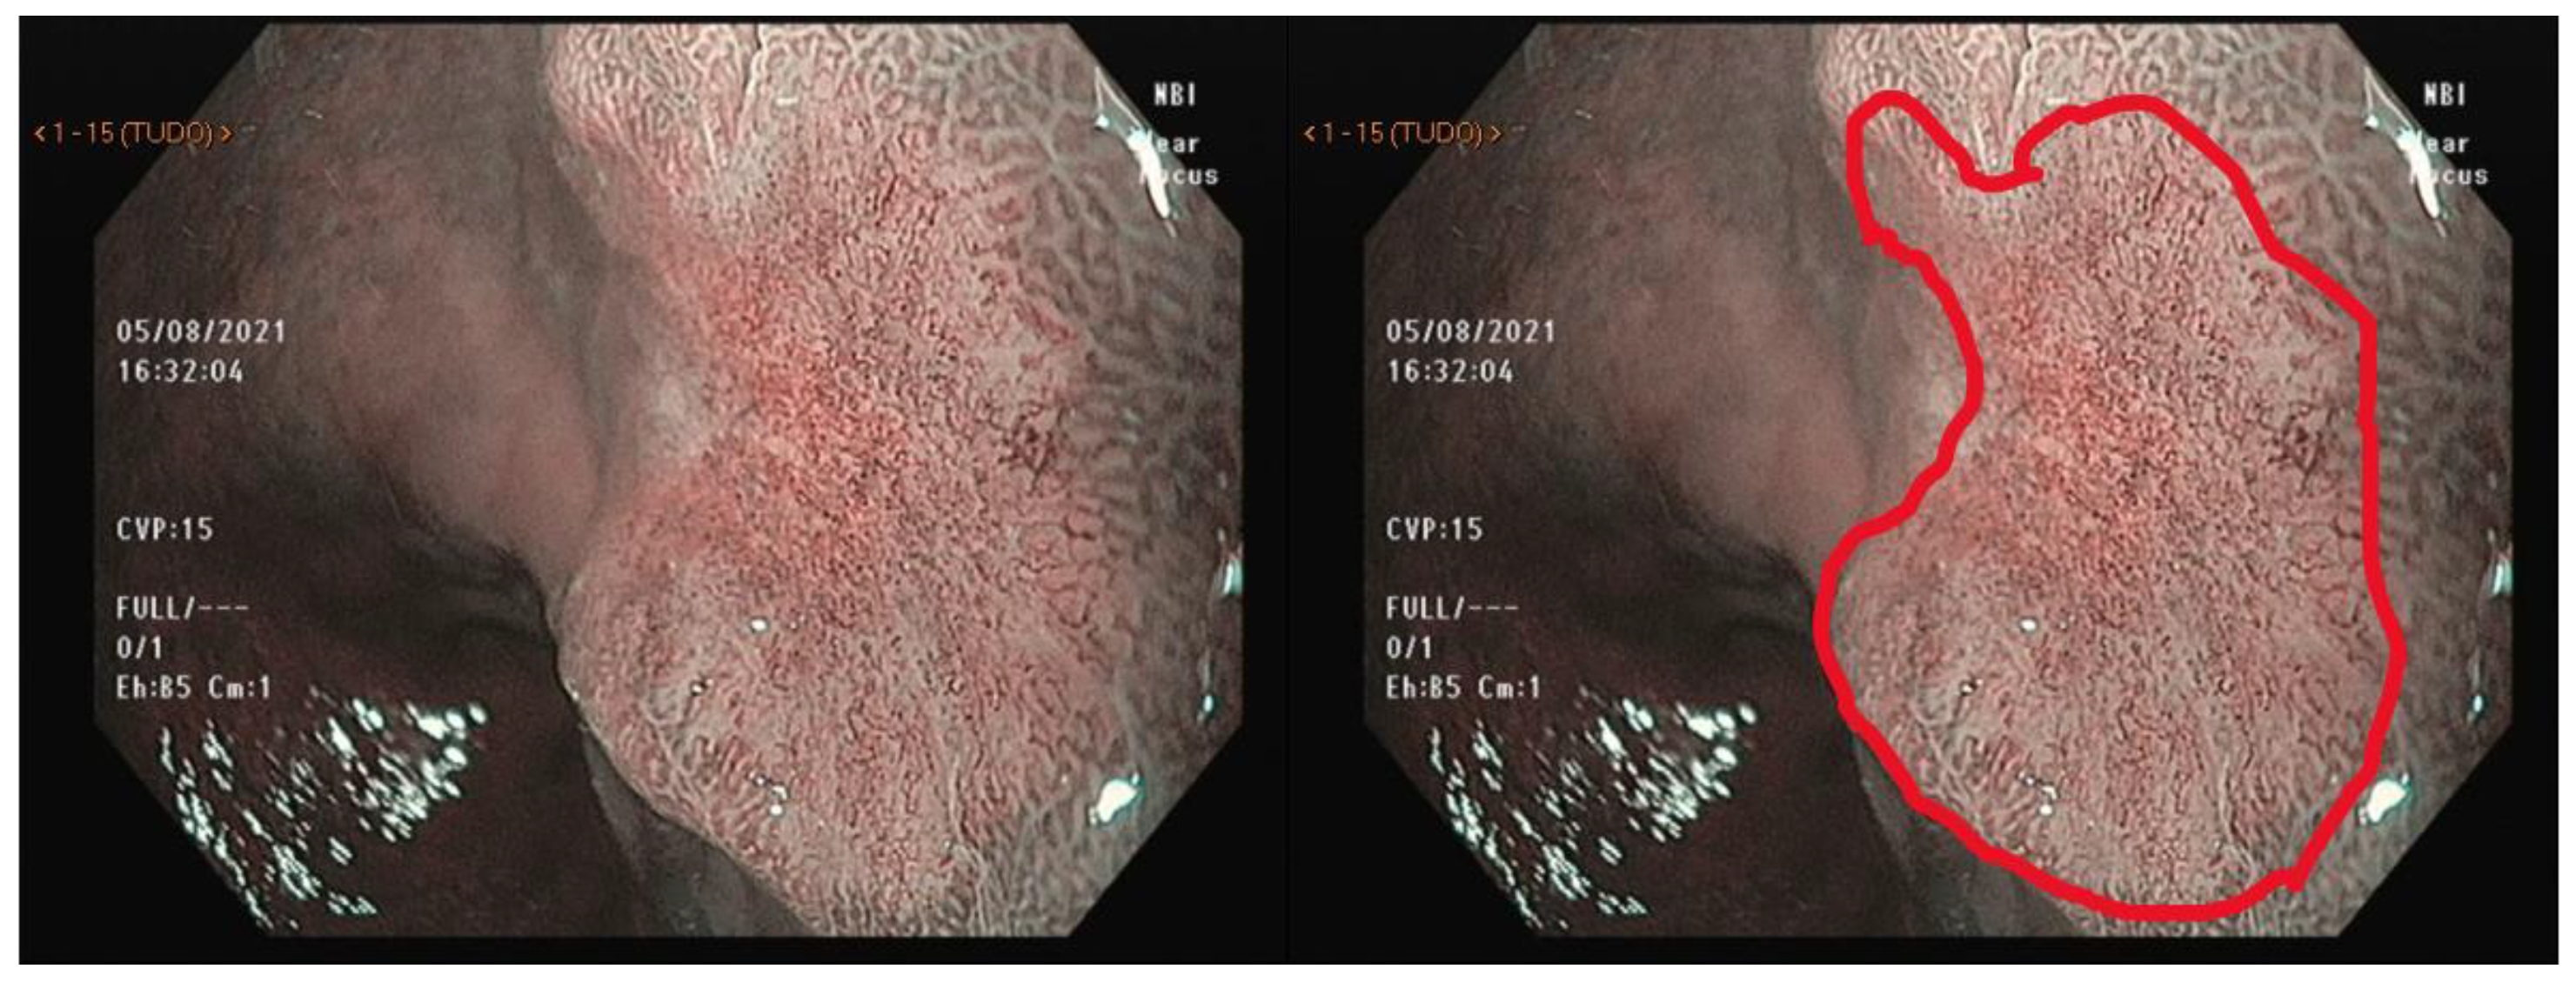

5. Virtual Chromoendoscopy

6. Magnifying Endoscopy